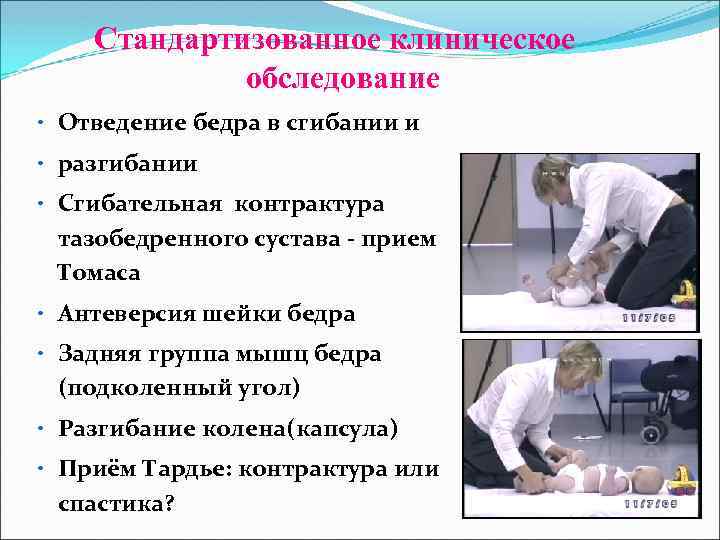

Стандартизованное клиническое обследование • Отведение бедра в сгибании и • разгибании • Сгибательная контрактура тазобедренного сустава - прием Томаса • Антеверсия шейки бедра • Задняя группа мышц бедра (подколенный угол) • Разгибание колена(капсула) • Приём Тардье: контрактура или спастика?